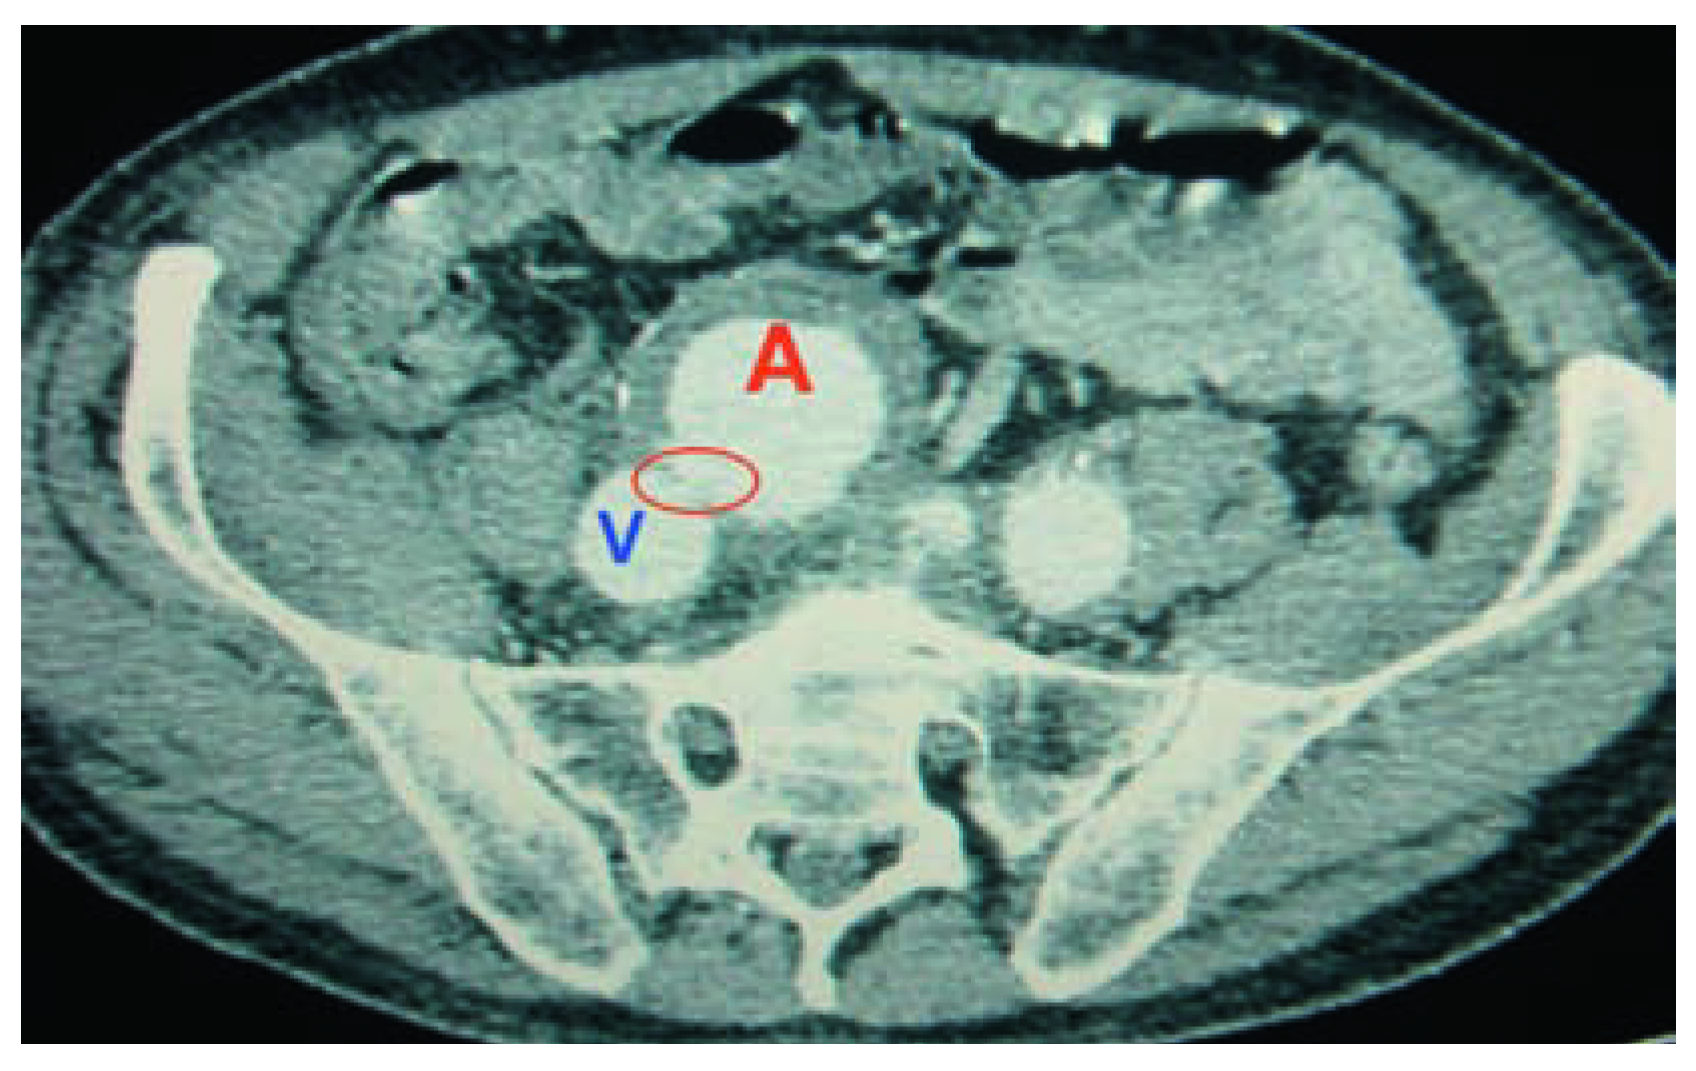

Die erneute Sonographie der Aorta zeigte eine Zunahme des Durchmessers des iliakalen Aneurysmas auf einen Durchmesser von 5,5 cm. Das notfallmässige Angio-CT bestätigte die klinische Verdachtsdiagnose einer gedeckten Perforation des Aneurysmas mit iliokavalem Shunt.

In einer Aortographie zeigte sich nebst dem stabilen infrarenalen Aortenaneurysma (4,5 cm) ein partiell thrombosiertes iliakales Aneurysma von 5,5 cm mit massivem Shunt in die Vena cava inferior, wobei die Ruptur der Arterienwand proximal des Abgangs der rechten A. iliaca interna lag. Es fand sich kein extravasales Kontrastmittel (Abb. 1–3).

Abbildung 1. Konventionelles CT mit AV-Fistel (

) zwischen dem Aneurysma der Arteria iliaca communis (A) und der Vena cava inferior (V). (Wir verdanken die Abbildung Frau Dr. med. Kathrin Stoob, Fachärztin FMH Radiologie, Röntgeninstitut, Klinik Hirslanden, Zürich.).